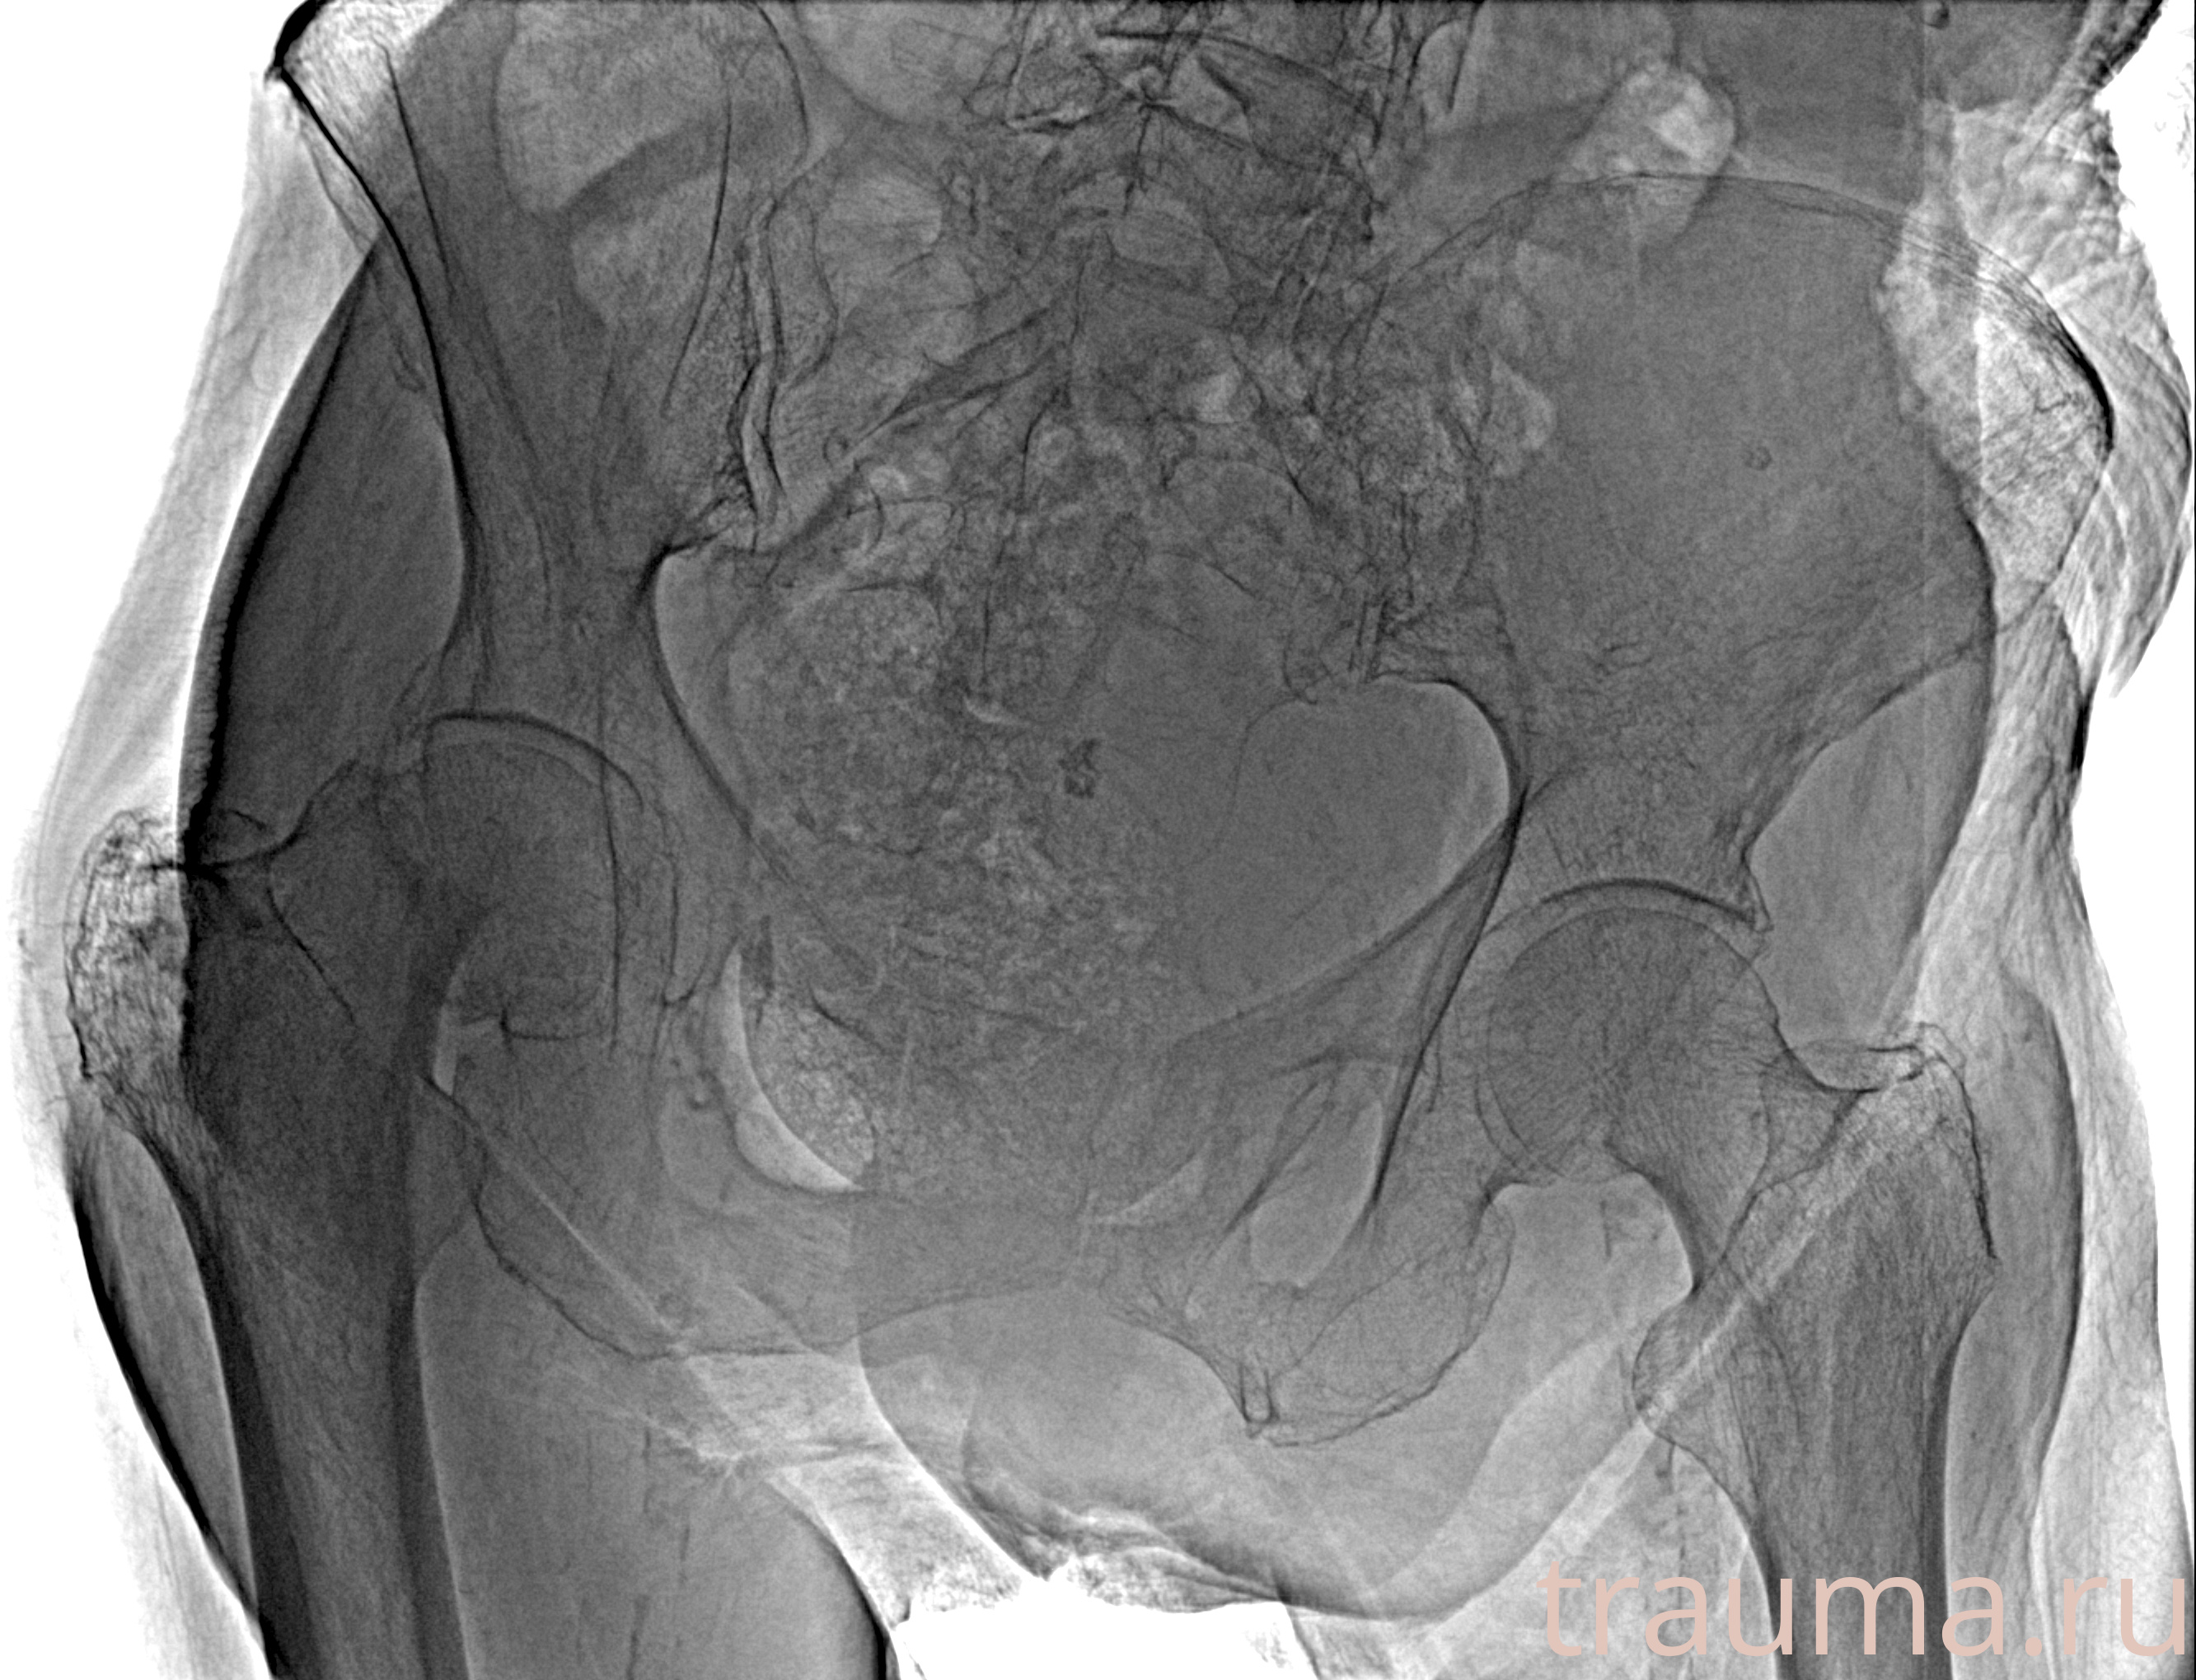

Рентген на дому: по вашему адресу приезжает врач-рентгенолог, травматолог-ортопед с мобильным рентгеновским аппаратом, проводит диагностику травмы или заболевания, делает необходимые рентгенограммы, дает рекомендации по дальнейшему лечению. Получить качественные снимки в домашних условиях возможно благодаря уникальной методике, разработанной МосРентген Центром для института  Склифосовского